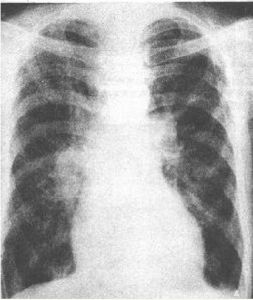

可無體徵異常或僅有雙肺乾羅音、哮鳴音。X線檢查可無異常,或輕度間質改變,邊緣模糊的肺紋理增多。

可聞水泡音或管狀呼吸音。X線檢查出現斑片狀、以及融合成大片狀浸潤陰影。

3、X線檢查出現斑片狀或大片狀浸潤陰影,毛玻璃樣改變。

左心衰致心源性肺水腫

與ARDS的非心源性肺水腫有類似之處,如呼吸困難、呼吸增速、紫紺等。但左心衰竭起病急,不能平臥,咯血性泡沫痰,有心臟病病史,體徵或心電圖等異常。胸片可見典型心源性肺水腫的改變。